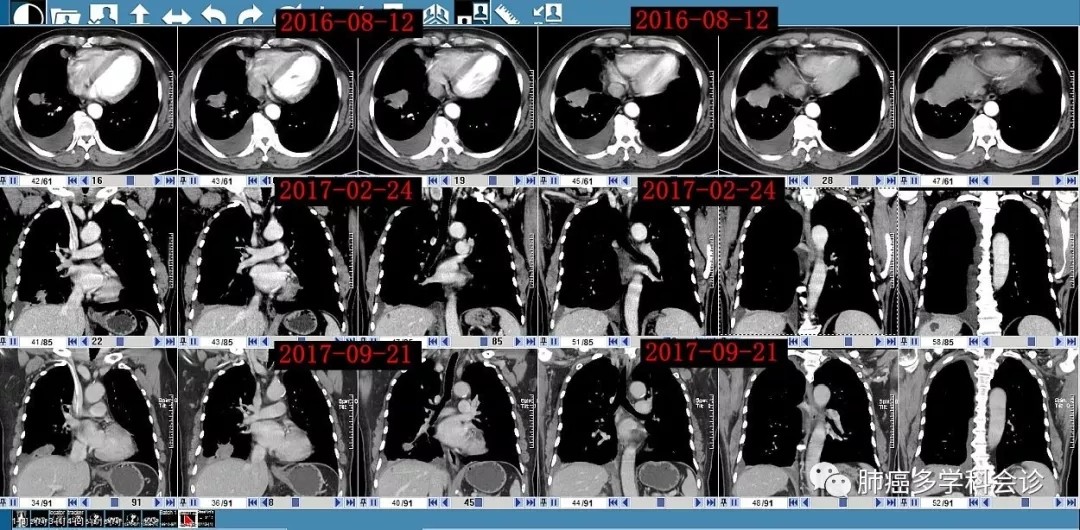

:患者早期接受化疗及后来TKI治疗期间肿瘤的变化(相对现在较缓慢):

患者在2016-08 ~ 2018-05在X省X院X科X病区先后进行了 6个双药联合方案的化疗(1-6线),最后发生腹腔淋巴结转移和腹膜腔转移,以下是该患者的化疗简史:

• 2016-08 ~ 2017-01“多西他赛+奥沙利铂”× 6 周期

• 2017-03 ~ 2017-06 “培美曲塞+奥沙利铂” × 5 周期,最后一次输液奥沙利铂过程中出现I型过敏反应(胸闷、呼吸困难、上肢与胸前皮肤红疹)。

• 2017-07 ~ 2017-10“培美曲塞+洛铂”× 3 周期。2017-09 胸腔灌注“白介素-2”

• 2017-12 ~ 2018-01 "多西他赛+吉西他滨" ×2 周期

• 2018-02 ~ 2018-03 "伊立替康+替吉奥" ×2 周期。

• 2018-04 复查 CT 示病情进展。周围血EGFR基因无突变。

• 2018-04“洛铂+依托泊苷” × 1周期。